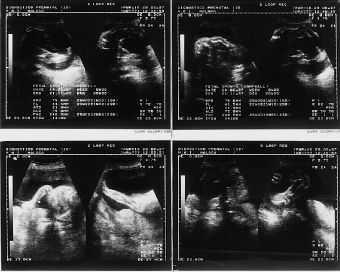

El examen ultrasonográfico, realizado en la Unidad de Diagnóstico Prenatal de nuestro hospital, en semana de amenorrea 28 demostró la existencia de un feto de sexo femenino con acortamiento de ambas tibias y peronés, con incurvación de fémures, con pies equinovaros y polihidramnios severo (Fig. 1). En controles ecográficos posteriores, se objetiva, un tórax angosto, un abdomen globuloso, con ausencia de cámara gástrica, importante acortamiento de fémures y la persistencia de un polihidramnios severo (Fig. 2) . En semana 31, se realiza el estudio citogenético del líquido amniótico, que nos revela un cariotipo masculino, 46 XY normal, y un nivel de alfafetoproteína en líquido amniótico de 2 mcg/ml.

Figura 1.Examen ultrasonográfico en semana de amenorrea 28: feto de sexo femenino con acortamiento de ambas tibias y peronés, con incurvación de fémures, con pies equinovaros y polihibramnios severo.

Figura 2.Control ecográfico en S.A. 35: un tórax angosto, un abdomen globuloso, con ausencia de cámara gástrica, importante acortamiento de fémures, con longitud correspondiente a S.A. 26 y la persistencia de un polihidramnios severo.